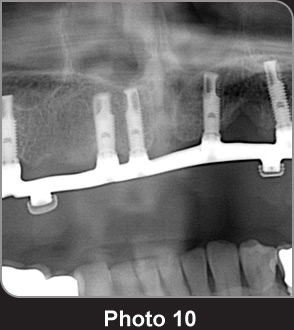

上顎金屬種植支架的OPG圖片。